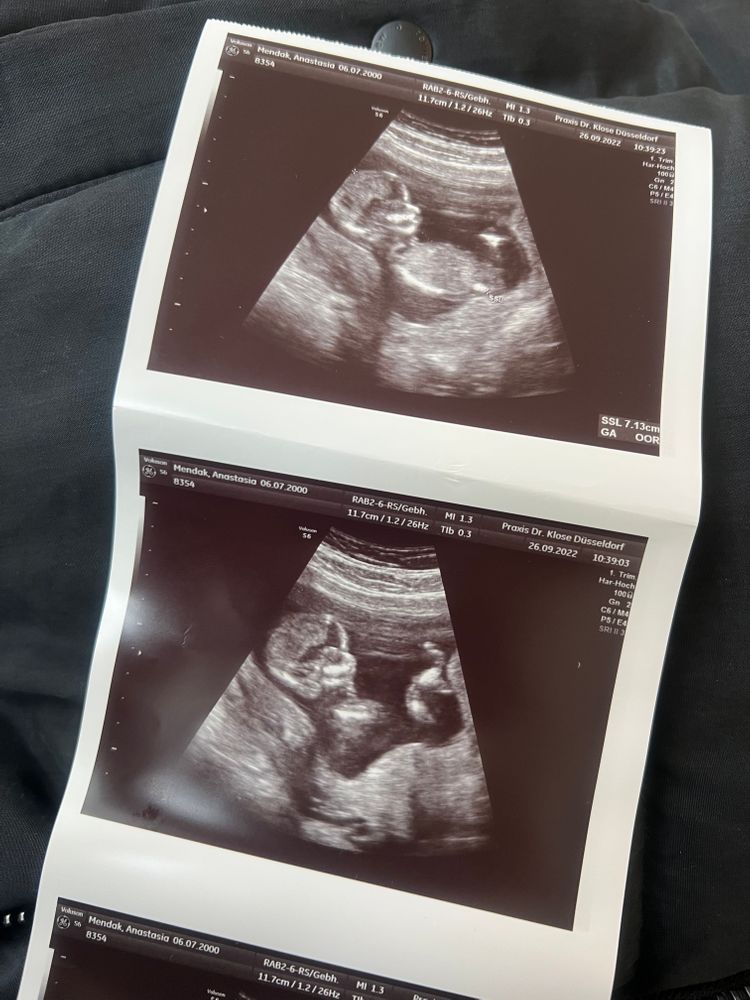

Почти закончился 6 месяц беременности а мне так и не могут сказать кто у меня родится. Через пару дней на узи, но не факт что скажут, старый аппарат и врач скорее не опытный. Я сейчас нахожусь на 25 неделе. Последнее фото было месяц назад на 21 неделе. На первом узи сказали что 80% мальчик(1фото). На втором узи сказали что ничего непонятно. На третьем сказали что возможно девочка, но ничего не видно. Помогите, пожалуйста, определить пол🐰

По таким фото не видно (ракурс и мелкие). Делают для точности узи попой снизу, чтобы видно было, что между ножек...странно,писюн не заметить, может, и правда тогда, пол женский. Но это всё домыслы. Сделайте в другом месте узи

Хотя знаете, мне на самом нижнем кажется, что девочка. Там похоже на "кофейное зёрнышко ".

У вас фото какие-то не удачные , в том смысле , что на них не видно пол, даже предположить не возможно. Я на последних двух вообще не пойму что изображено.